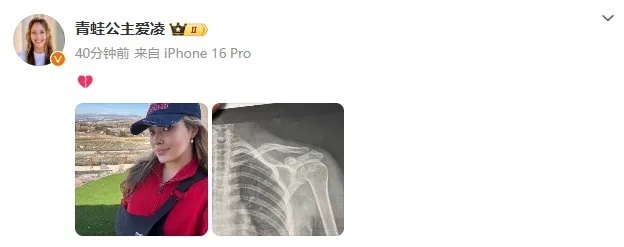

今年3月9日,谷爱凌在社交媒体晒出肩部骨折的X光照片,并配上一个心碎的表情,随后相关话题登上热搜。